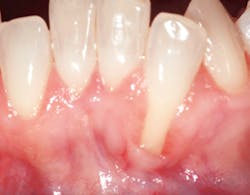

Identification of gingival recession can serve as a perfect example of how the hygienist can make a difference. This condition is a seemingly minor problem that many simply associate with esthetics. However, when patients have gingival recession with bleeding pockets it could be an open source of infection. Patients can have a healthy mouth and practice good oral hygiene and yet, still experience site specific areas of gingival recession. Most are not even aware of it. Areas of recession can be caused by toothbrush abrasion and trauma.3 All too often it is regarded as an unavoidable part of the aging process.

In some patients, areas of recession are stable based on previously documented measurements with no requirement for specific intervention or treatment . But with other patients, we know otherwise. Recession can lead to the exposure of the tooth's root surface, causing esthetic problems and sensitivity. Early diagnosis and treatment of gingival recession is important because the situation can worsen to where predictable root coverage isn't possible and esthetics become compromised. Many hygienists and clinicians see this problem in patients; however, they don't necessarily inform them so they could opt for treatment sooner. Correct initial diagnosis is key.4 The goal is to deliver optimal treatment outcomes and provide our patients with more predictable results.